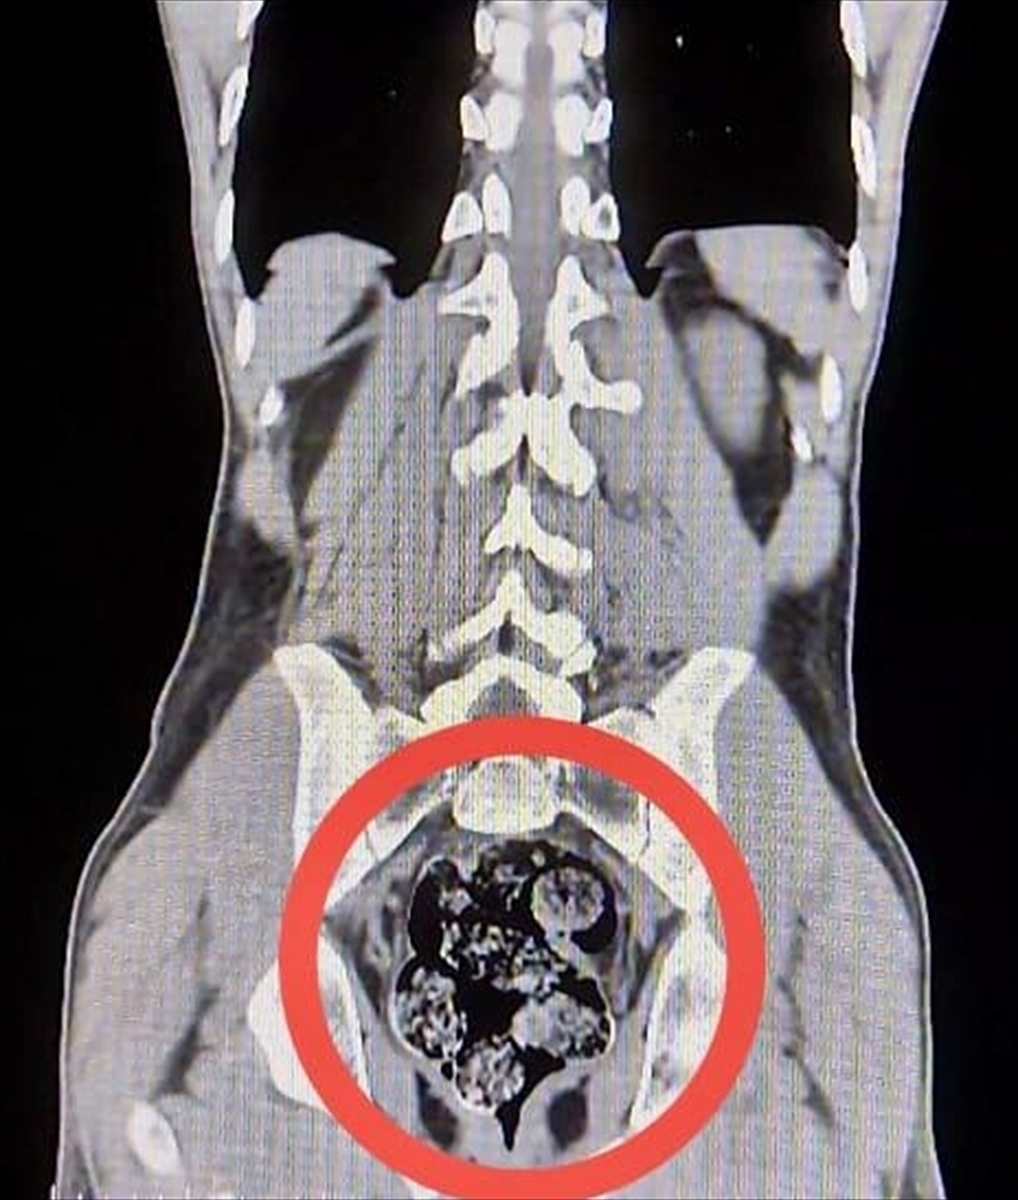

Yolcu otobüsüyle seyahat eden zanlıların üzerlerinde yapılan ilk aramada herhangi bir yasak madde bulunamadı. Ancak Harakani Devlet Hastanesi'nde gerçekleştirilen detaylı muayene, farklı bir durumu ortaya çıkardı. Zanlılardan Amır Rafıeı S.'nin mide ve bağırsaklarında, 7 parça halinde toplamda 203,02 gram sentetik uyuşturucu tespit edildi. Bu durum, uyuşturucu kaçakçılığının sınır tanımaz hale geldiğini çarpıcı bir biçimde gösteriyor.

Uyuşturucunun iç organlardan çıkarılması cerrahi müdahaleyle sağlandı. Bu yöntem hem taşıyan kişi hem de böyle bir naklin gerçekleştirildiği çevre için büyük tehlikeler taşımakta. Güvenlik uzmanları, bu tür olayların artış göstermesinin, organize suç örgütlerinin yeni yöntemler geliştirdiğine işaret ettiğini belirtiyor.